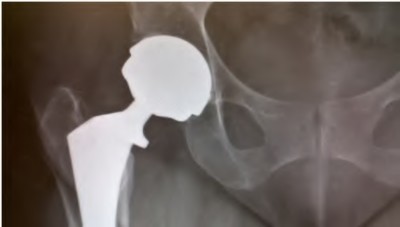

A 78-year-old female sustains a periprosthetic femur fracture 10 years after a cemented THA. Radiographs show a fracture around the tip of the stem with a loose femoral component and poor proximal bone stock, but adequate diaphyseal bone.

What is the most appropriate surgical treatment?

A 75-year-old female sustains a periprosthetic femur fracture around a cemented polished taper slip stem. Radiographs demonstrate a fracture around the tip of the stem. The stem is radiographically loose, but the proximal bone stock is excellent (Vancouver B2).

What is the gold standard surgical management?